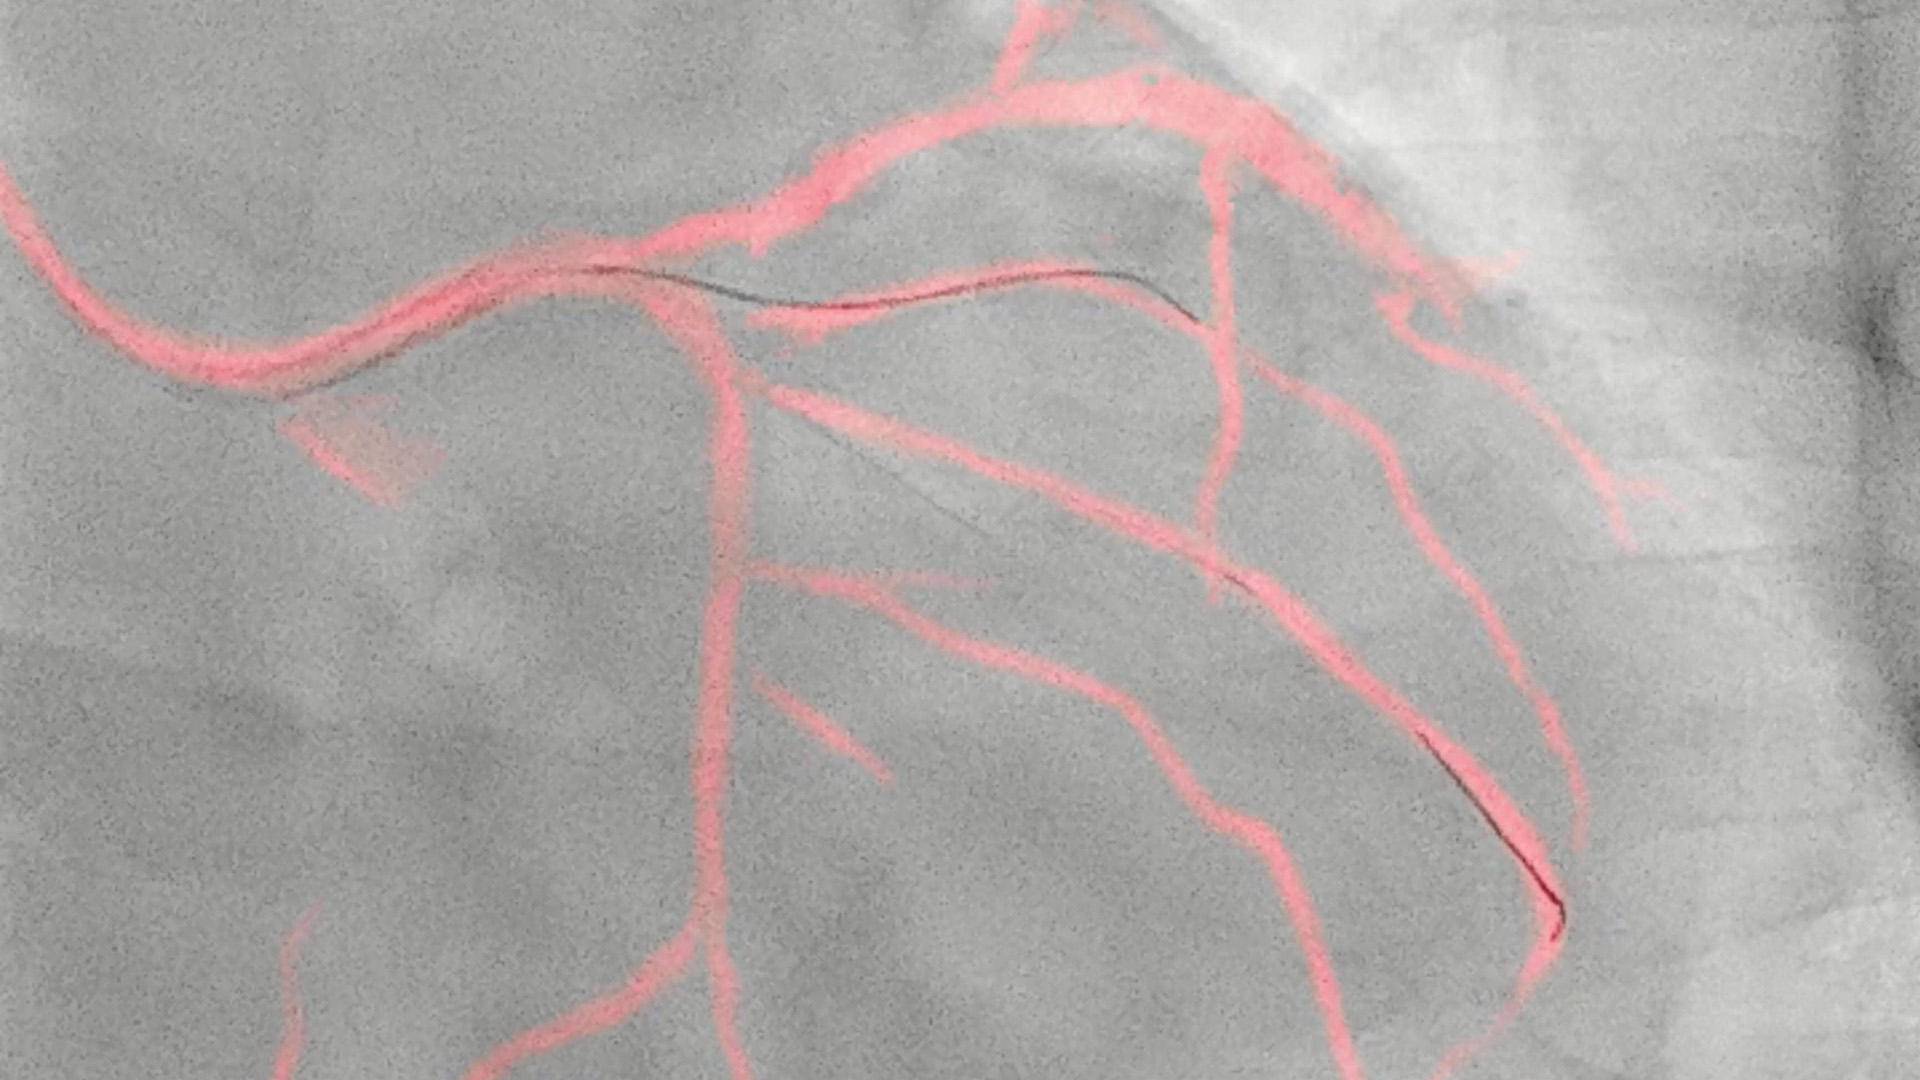

Coronary suite

Philips coronary suite transforms complex PCI procedures into confident care. Advanced clinical and workflow applications, therapeutic and diagnostic devices, and leading services, all working together to efficiently support every step or coronary procedures.